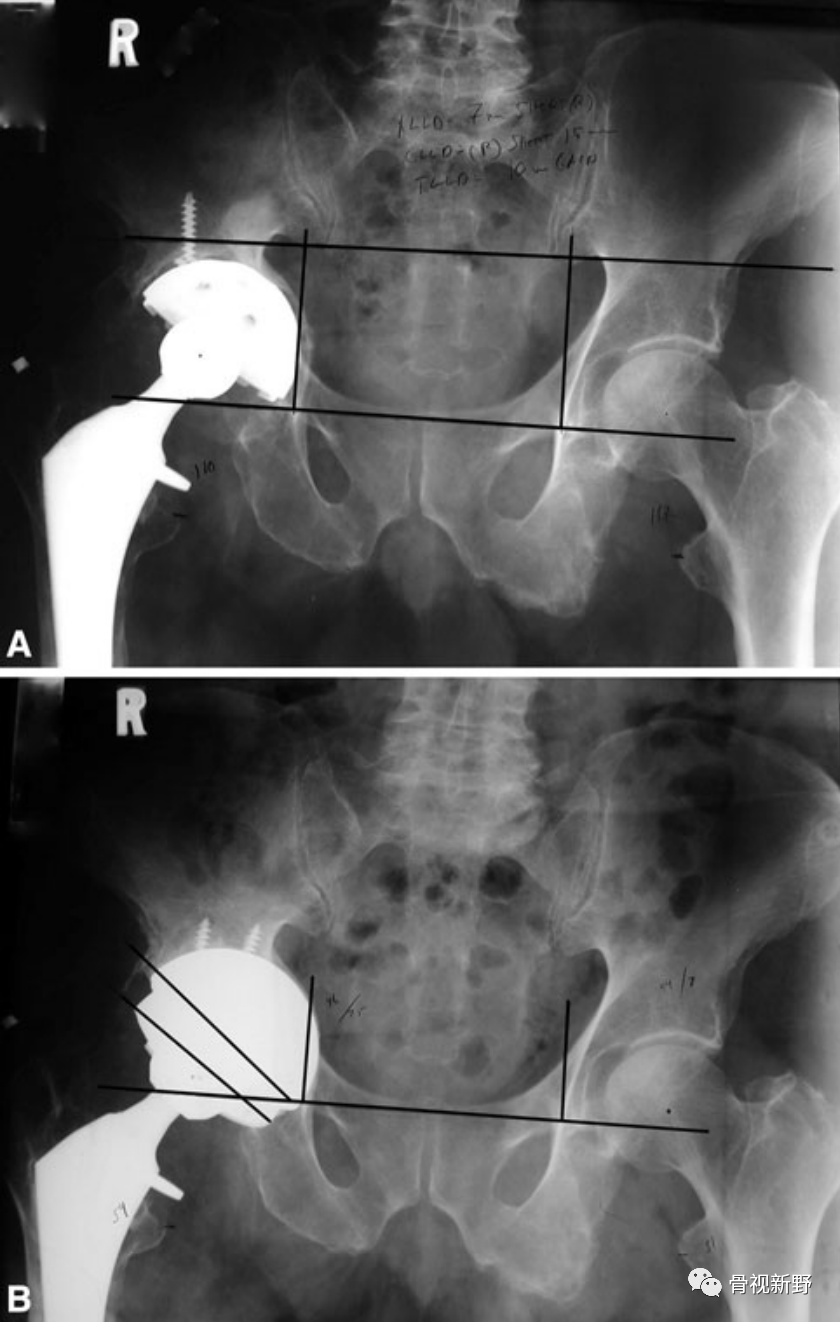

Case 1: Paprosky IIIb

男性,78岁。因右髋部骨折,于25年前行右髋THA。入院前半年开始出现右髋部疼痛、活动受限,加重1月。影像资料提示假体松动、移位;股骨侧及髋臼侧严重骨缺损(Paprosky IIIb )。

完善术前常规检查后,择期行翻修术:髋臼侧以cup-in-cup技术翻修;股骨侧以水泥柄翻修。

术后X光片